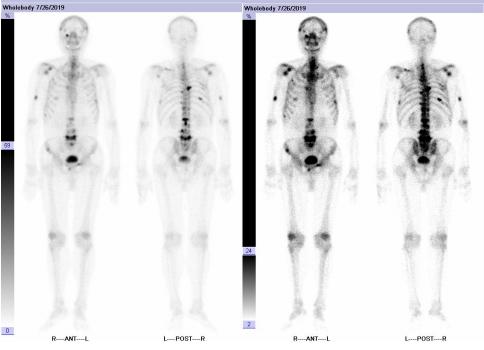

全身骨显像:肿瘤多发骨转移。

图2 患者起始治疗前全身骨显像

2020年5月13日,复查全身骨显像示:考虑为肿瘤骨转移,与上次检查比较右侧第8前肋为新增病灶,其余病灶数目较前减少。

图5 患者复查骨显像状况